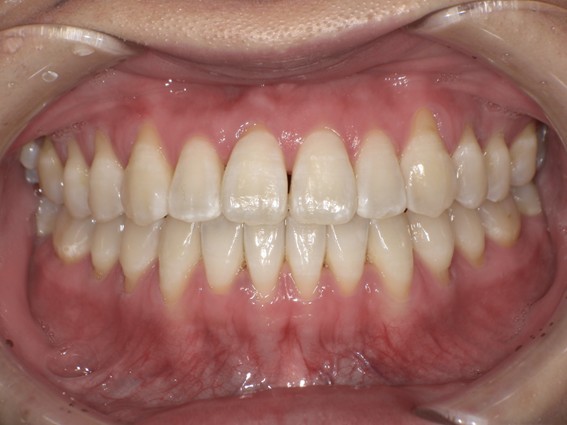

| 主訴 | 前歯が逆に噛んでいる。 |

| 治療内容 | 表側ワイヤー矯正、ジルコニア補綴を行いました。 |

| 治療費 | ワイヤー矯正660,000円(税込) ジルコニア176,000円(88,000円×2歯)(税込) |

骨格性Ⅲ級・前歯部反対咬合の症例でした。反対咬合のまま治療していた前歯のサイズ不調和を、表側ワイヤー矯正とプロビジョナルクラウンで調整。正中を整え、犬歯・臼歯ともⅠ級、適切なオーバージェット(上下前歯の前後的な距離)・オーバーバイト(上下前歯の垂直的な重なり)に仕上げました。